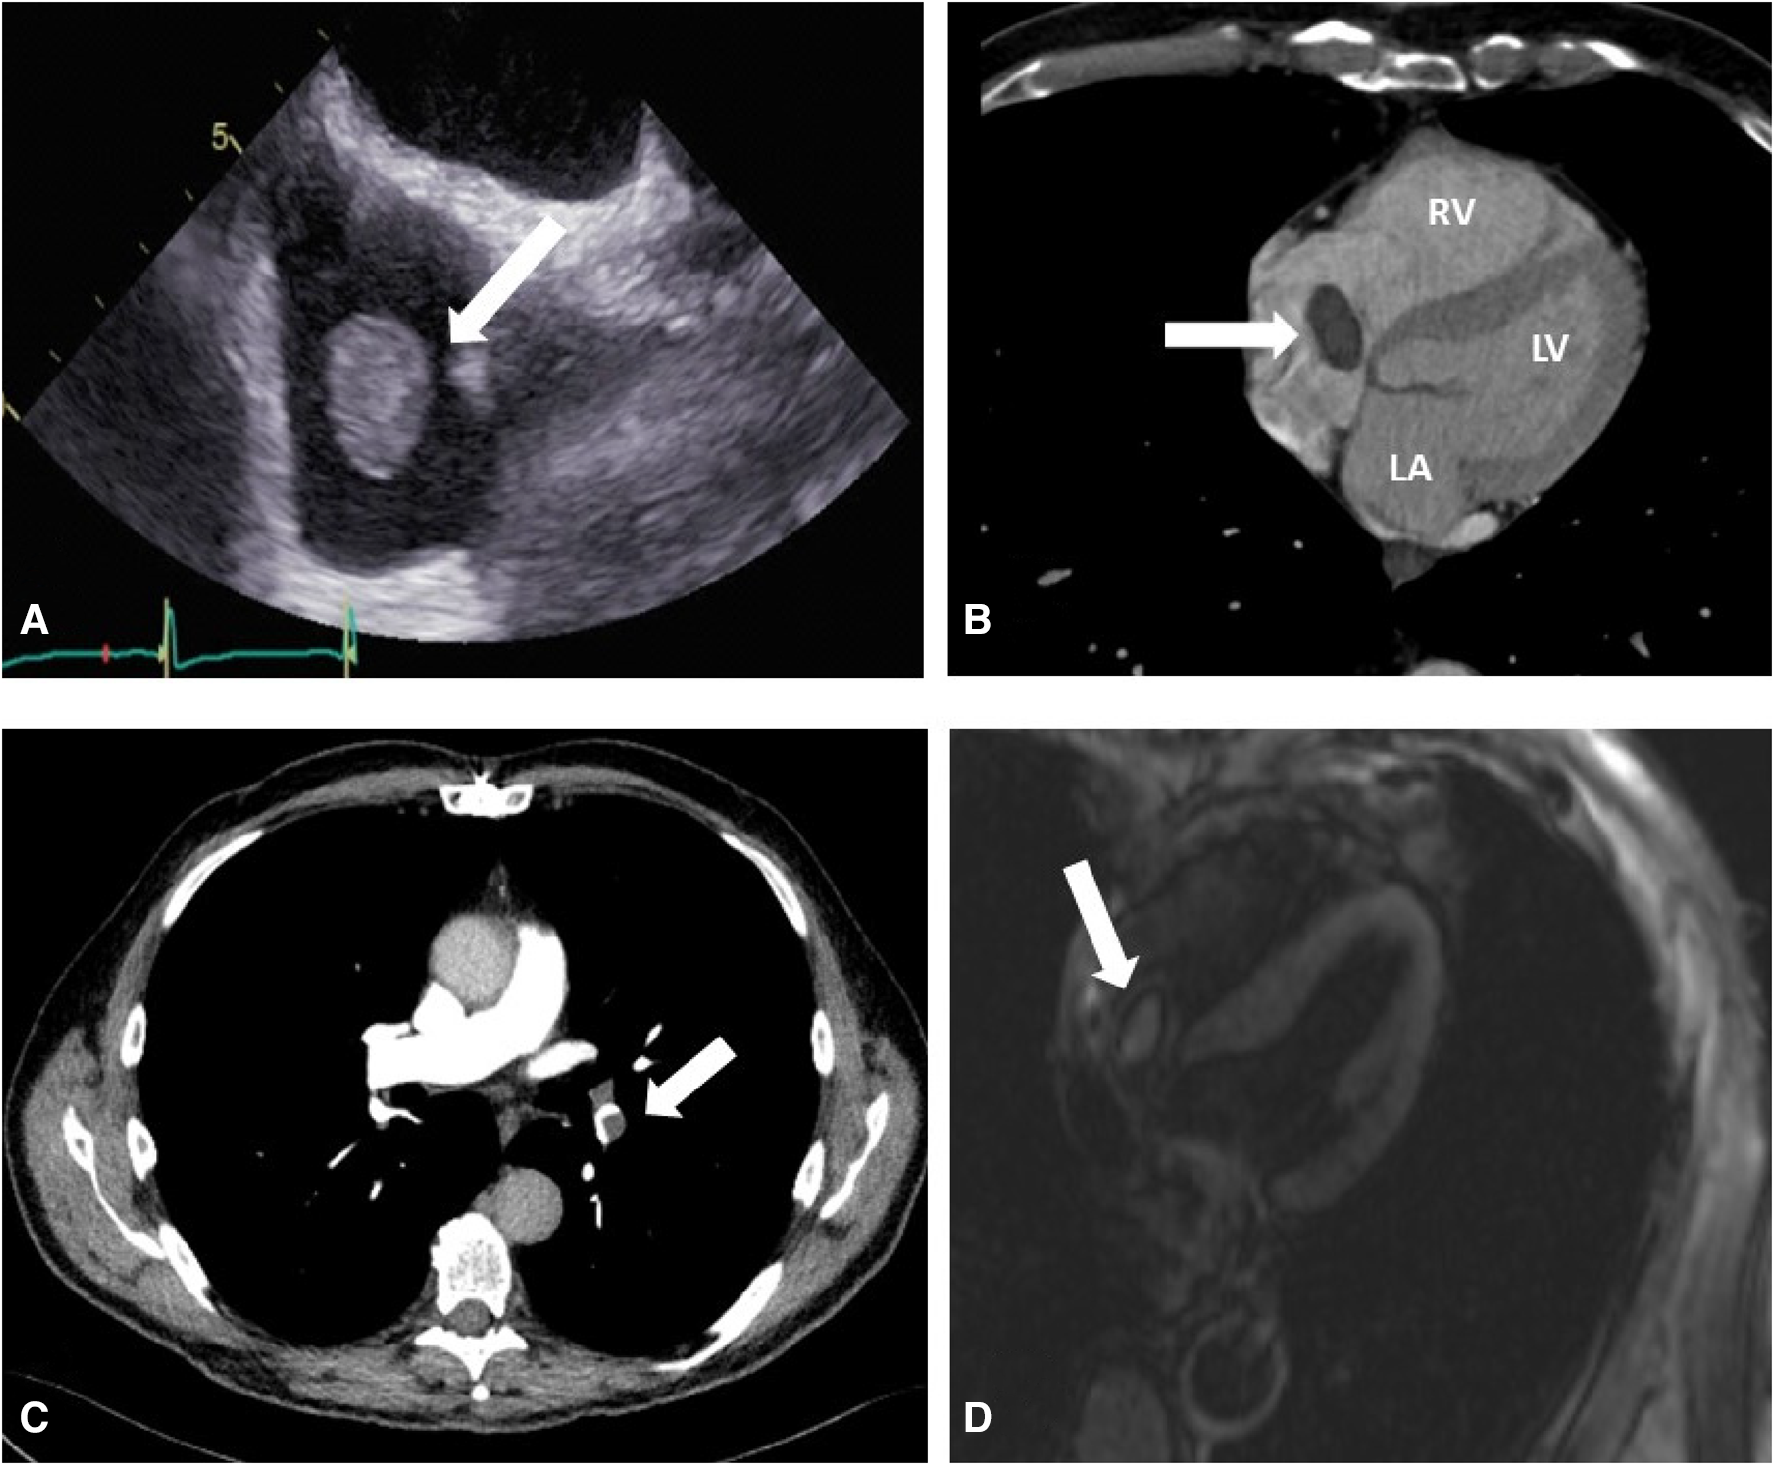

A 72-year-old male patient who had undergone a Bentall operation with a biological composite graft and closure of a patent foramen ovale 18 months before, presented with an incidental new RA mass during a follow-up echocardiography. Transesophageal echocardiography and thoracic CT angiography confirmed the presence of the right atrial mass and its location on the Eustachian valve (Figures 1A,B). Moreover, an incidental non-occlusive pulmonary embolism in the left inferior lobe pulmonary artery was diagnosed (Figure 1C). Despite 2 months of oral anticoagulant treatment, the size of the mass did not decrease. An MRI study confirmed the size and location of the mass in the RA and provided further evidence of central enhancement, which raised the suspicion of tumoral lesions (Figure 1D). After consulting with the local Heart Team, the decision to proceed with surgical treatment was made in order to prevent pulmonary embolization and obtain a definite diagnosis of this RA mass.

Figure 1

(A) Preoperative transesophageal echocardiography shows a mobile right atrial mass (arrow) on the Eustachian valve. (B) Preoperative thoracic CT angiography showing the right atrial mass (arrow), right ventricle (RV), left atrium (LA), and left ventricle (LV). (C) Preoperative thoracic CT angiography showing pulmonary embolization (PE) on the inferior branch of the left pulmonary artery (arrow). (D) MRI imaging that shows a central mass enhancement (arrow) on the Eustachian valve.

Oral anticoagulant treatment is considered the first-line treatment in the presence of intra-cardiac thrombi (7). Because of the size of the RA, the mass did not decrease following 2 months of oral anticoagulant treatment, and suspicion of an intra-cardiac tumor was raised. This suspicion was further supported by central mass contrast uptake observed in the MRI study (Figure 1D). Cardiac MRI can be used to differentiate between intra-cardiac thrombi and tumors (8). Thrombi typically do not show contrast uptake and appear dark on LGE (late gadolinium enhancement), with a surrounding area of high uptake from adjoining blood or myocardium. Conversely, tumors exhibit central contrast uptake and delayed enhancement, as observed in our case, thus prompting surgical treatment. Although cardiac MRI has a high accuracy, in this particular case, it produced a false positive result (9).